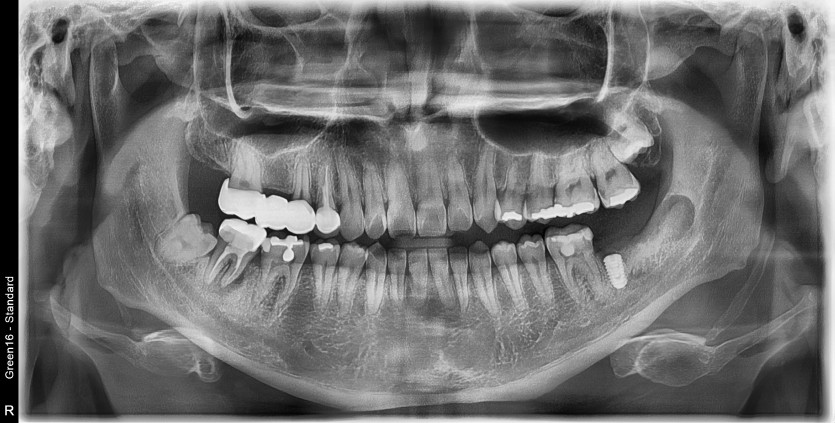

#38 사랑니 발치 (#37 발치 포함)

구강 외과 전문의가 당일 발치했습니다.